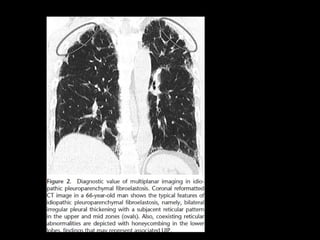

NSIP Histología • Continuode componente celular a fibrosis • Plasmocitos y linfocitos • Engrosamiento intersticial por acumulación de colágeno • Homogeneidad • Biopsia es incompatible con otros patrones

NSIP TC • Vidrioesmerilado bilat y simétrico, LS Reticulación fina, BQ por tracción, disminuciónd e volumen pulmonar, panalización leve Consolidaciones Exacerbaciones menos comunes que FPI • Pronóstico depende del grado de fibrosis • Celular: 100% sv Fibrótico: 5 años SV